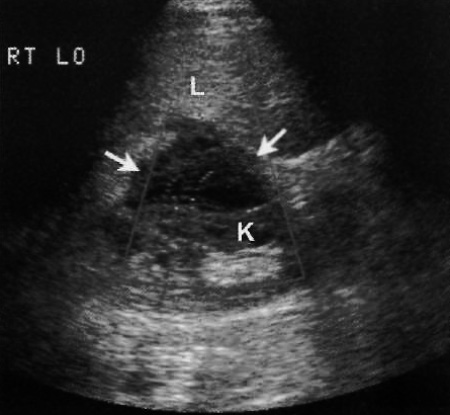

ПТ-ЛПЗ на УЗИ определяется как гипоэхогенное образование, размером от 1 до 4 см, в котором может наблюдаться васкуляризация. Патологические очаги могут возникать как в трансплантате печени, так и в отдаленных органах (ретроперитонеальных лимфатических узлах, почках, надпочечниках, селезенке, кишечнике). Бывают случаи диффузного поражения ПТ-ЛПЗ печени или области ворот печени, что в последствии вызывает обструкцию желчных протоков (фото 7).

Фото 7. Посттрансплантационное лимфопролиферативное заболевание. Ультразвуковое изображение правого верхнего квадранта живота: стрелками обозначено гипоэхогенное сосудистое образование размером 4 см, локализованное между почкой (K) и печенью (L). Гистологический анализ подтвердил диагноз ПТ-ЛПЗ